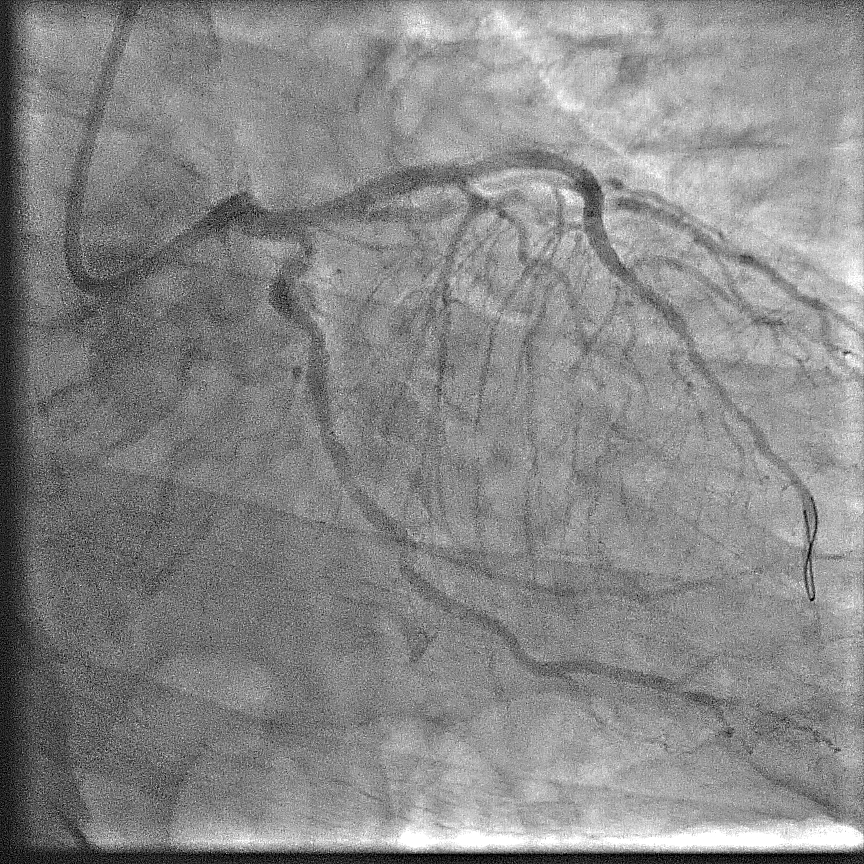

Relevant Catheterization Findings

Angiography showed extensive calcification in the left and right coronary arteries, with severe stenosis at the left main ostium, severe in-stent restenosis at mid LAD, and severe, tortuous stenosis at the ostium and proximal LCx. The RCA was severely diffuse diseased with heavy calcification. The SYNTAX score was 58; BCIS CHIP score 7/13 - a very high risk and complex anatomy for PCI. STS surgery score risk for mortality was 3%; mortality and morbidity 18%.

The case was referred to cardiac surgeon. Due to extensive calcification of the aorta, surgery was deemed highly challenging. With surgery declined, a staged procedure of PCI and transcatheter aortic valve replacement (TAVR) was planned. Throughout, contrast use was minimized to reduce renal injury.First Procedure: Initial PCI targeted the left coronary system. Pre-dilation was performed at left main ostium, followed by at the most obstructive lesion in the LCx to reduce the risk of ischemia in subsequent interventions. The mid-LAD was treated with a drug-eluting balloon (DEB), followed by the LCx with DEB. Finally, the left main ostium was stented with a drug-eluting stent (DES), achieving a favourable outcome. Total contrast volume used was 28 mL.Second Procedure: The next day, PCI was performed on the RCA. Despite the challenging ostial lesion, positioning of the guiding catheter (AL1) was successful. Balloon pre-dilation and placement of two DESs in the proximal RCA achieved satisfactory result. Total contrast used was 31 mL. The patient experienced significant relief from angina following these interventions.One Month Later: TAVR was performed using an Evolut Pro+. Due to severe iliofemoral and aortic calcifications, device delivery was challenging. TAVR was ultimately succesful; peak aortic valve gradient was decreased from 50 mmHg to no residual gradient.